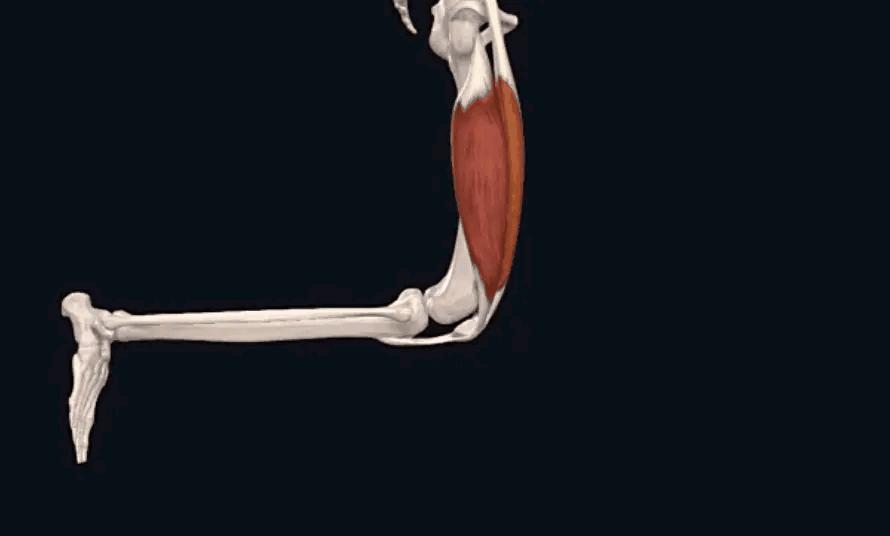

主要是长在骨头上的肌肉和韧带。在膝盖的四周都有不同的肌肉、韧带,从不同的角度发力来维持膝关节和膝盖骨的稳定;倘若哪一侧太弱,其他侧太强,就会打破原有的稳定状态,出现不同的腿型、不同方向的膝盖骨移位。

2.其次,再来看一看,当您屈、伸腿时,膝关节具体是怎么移动的?

正常情况下 ,如动图所示,在您屈膝(弯腿)的时候,膝盖骨(俗称菠萝盖)会往内下方移动;而伸膝(伸腿)的时候,膝盖骨会往外上方移动。

这里说的锻炼,不是告诉您去跑步,而是有针对性地加强腿上的力量训练。